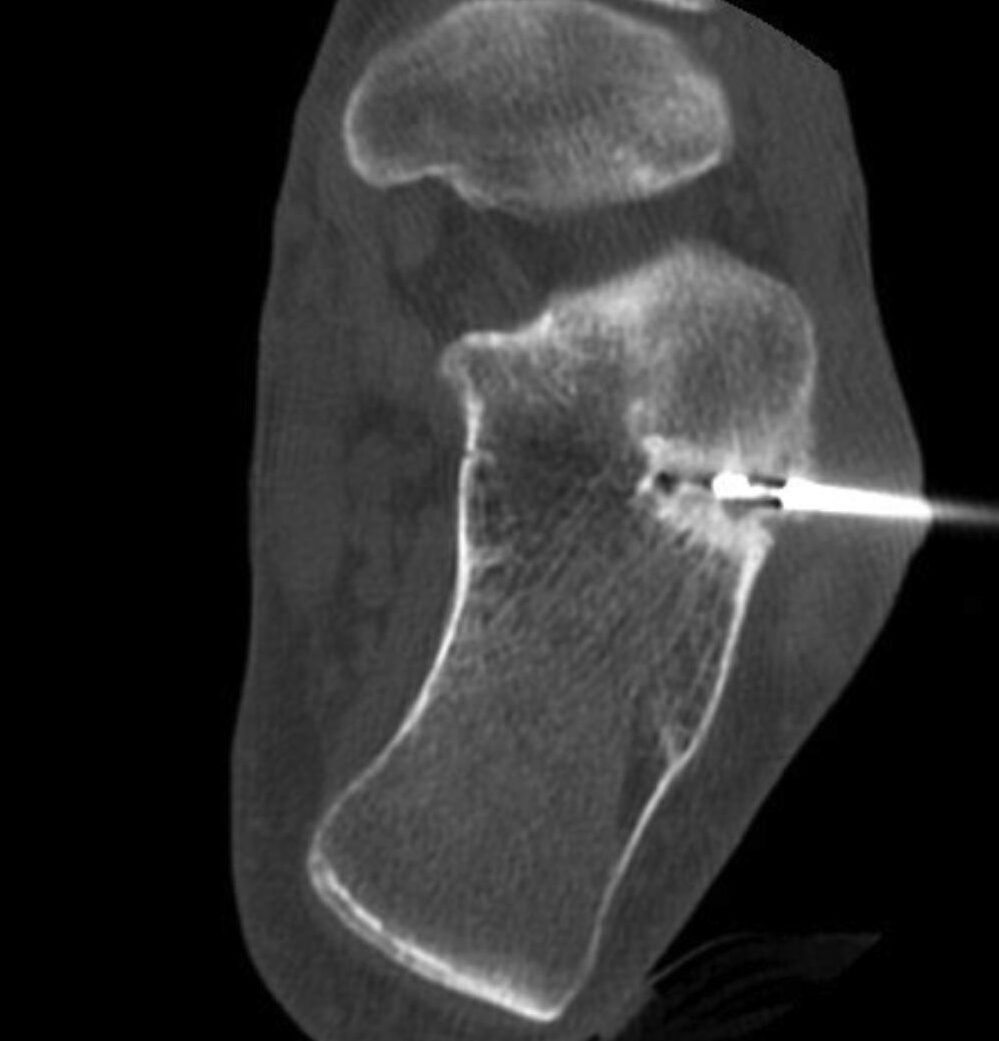

El diagnóstico del Osteoma Osteoide se realiza mediante exámenes de imagen como radiografías y tomografías computarizadas. Estos exámenes permiten identificar las características óseas del tumor y confirmar su presencia. En algunos casos, también puede ser necesario realizar otros exámenes como resonancia magnética o cintigrafía ósea para obtener más información sobre el tumor.